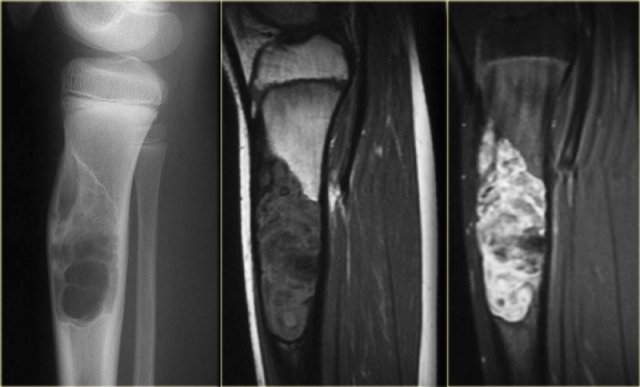

Study the images of a 14-year old boy and then continue reading.

The findings are:

• Radiograph.

Mixed lytic-sclerotic lesion in distal femur metaphysis and diaphysis with possible extension to the epiphysis.

The matrix of the tumor is bone.

Diagnosis: osteosarcoma.

• MRI.

Coronal image confirms the epiphyseal involvement with reactive edema.

Axial image shows the circumferential soft tissue extension and relationship to the neurovascular structures.